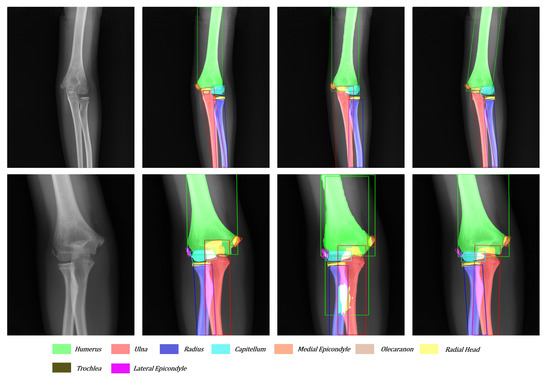

The dataset contains 1274 pediatric elbow radiographs with scales from 1140 × 1432 to 1780 × 1600 . Radiographs are screened between January 2003 and October 2010. Among them, 692 radiographs are anterior and 582 are lateral. The whole dataset is separated into training, validation, and test with a ratio of {3:1:1}. As shown in Figure 8a, there are nine bone categories: humerus, radius, ulna, capitellum, radial head, olecranon, trochlea, medial epicondyle, and lateral epicondyle. Figure 8b shows the age distribution. Each bone in this dataset is annotated with an OBB and a mask. Three senior orthopedic specialists cooperate in labeling ground truths with the annotation tool. The tool allows the specialist to wrap any bones with a set of dots in each radiography. The radiographs have been approved by the local ethics committee for this study and we hid the patient’s information before providing it to the investigators.

Figure 8. Statistics of (a) Bone category distribution. (b) Age distribution. Ul: Ulna; Ra: Radius; Hu: Humerus; Ca: Capitellum; Rh: Radial Head; Mp: Medial Epicondyle; Ol: Olecranon; Lp: Lateral Epicondyle; Tr: Trochlea.